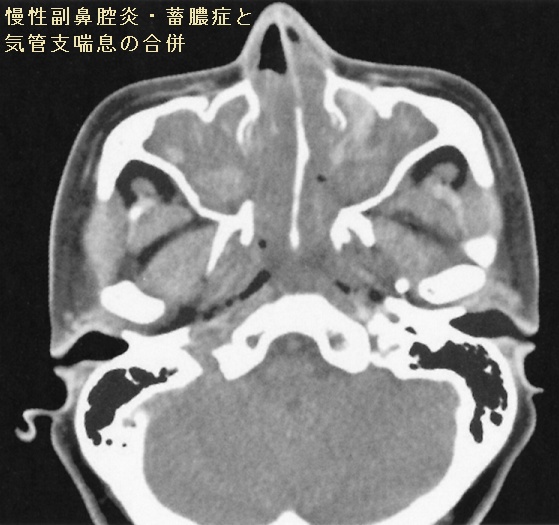

慢性副鼻腔炎/蓄膿症は、鼻腔周囲の空洞(副鼻腔)における慢性炎症です。副鼻腔の粘膜が腫れて、鼻腔への粘液排出が妨げられると、膿(うみ)となってたまります。

上顎洞が好発部位。炎症が長期化すると、鼻茸(はなたけ、鼻ポリープ)が発生します。

慢性副鼻腔炎/蓄膿症と気管支喘息の関連は深く、一方で、甲状腺と気管支喘息にも強い関連があります(甲状腺と気管支喘息)。気管支喘息を持っていると、甲状腺疾患または慢性副鼻腔炎/蓄膿症を合併している確率が高くなります(Pediatr Pulmonol. 2016 Sep;51(9):901-7.)。

- 慢性副鼻腔炎/蓄膿症は気管支喘息の増悪、難治化の原因

慢性副鼻腔炎/蓄膿症で鼻茸(はなたけ、鼻ポリープ)を伴うと気管支喘息の合併率が高い

気管支喘息では健常人と比べ、副鼻腔CTで異常を認める率が高い

よって自ずと慢性副鼻腔炎/蓄膿症は甲状腺の病気に影響します。

通常の好中球性慢性副鼻腔炎にマクロライド療法を行うと、気管支喘息も改善します(約4週間で改善が見られ、6カ月間投薬を続けます)。